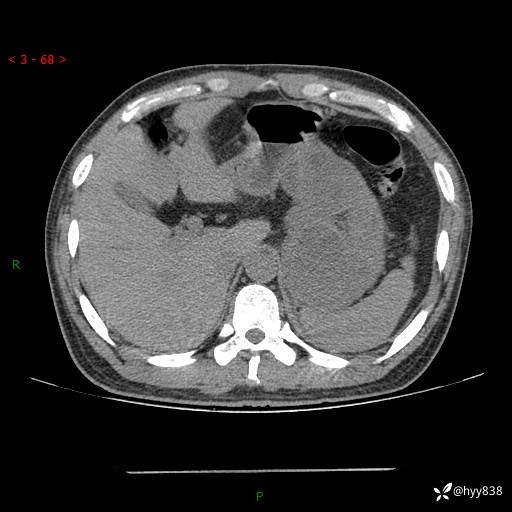

病例39岁/女,左侧腰痛入院。腹腔囊实性肿块,定位、定性---结果公布~

性别:男

年龄:39岁

简要病史:左侧腰痛待查,CT发现腹腔占位

腹部CT平扫+增强